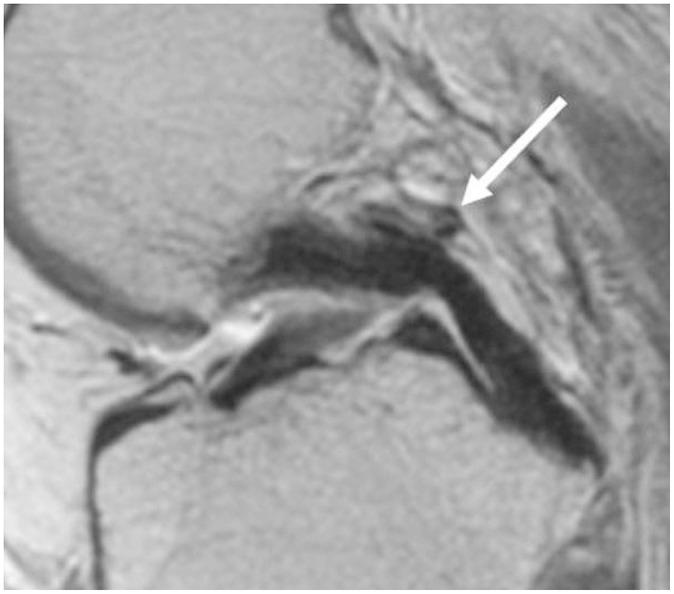

To accurately interpret knee MRI, it is important not only to know the basic meniscal anatomy but also to distinguish it from that under pathological conditions. Thus, it would be helpful to know the normal meniscus variants (false positives) that could be mistaken for meniscal tears, and tears that could easily be missed and incorrectly diagnosed as normal (false negatives). False positives include synovial recesses, meniscal flounce, the relationship between the popliteus tendon and lateral meniscus, transverse ligament, the anterior root of the meniscus, and meniscofemoral ligament. False negatives include focal radial tears, flap tears, posterior root tears, meniscocapsular separation, and discoid meniscal tears. In this pictorial essay, we reviewed the imaging data obtained in the aforementioned cases.

为了准确解读膝关节磁共振成像(MRI),不仅要了解半月板的基本解剖结构,还要将其与病理状态下的情况区分开来。因此,了解可能被误诊为半月板撕裂的正常半月板变异(假阳性)以及容易被漏诊并错误诊断为正常情况(假阴性)的撕裂情况会有所帮助。假阳性包括滑膜隐窝、半月板皱襞、腘肌腱与外侧半月板的关系、横韧带、半月板前根和半月板股骨韧带。假阴性包括局灶性放射状撕裂、瓣状撕裂、后根撕裂、半月板关节囊分离和盘状半月板撕裂。在这篇图文文章中,我们回顾了上述病例中获得的影像数据。